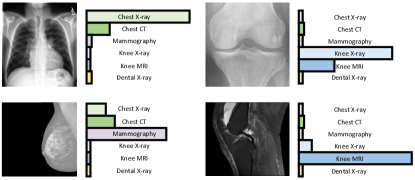

The generalizability of the CLIP pre-trained model becomes evident when applied to specialized areas such as medical imaging. Although originally trained on internet images and their textual captions, CLIP has demonstrated the capability to recognize and categorize medical images. Fig. 4 illustrates the generalizability of CLIP via domain identification, where the class token in the text prompt is substituted with the specific class name, such as “Chest X-ray”, “Mammography”, “Knee X-ray”, or “Dental X-ray”. Its zero-shot inference capability allows it to identify the domain of a given medical image without explicit prior training on such datasets. While further studies and validations are necessary, the preliminary findings suggest that the zero-shot capability of CLIP could reduce the dependency on extensive labeled medical datasets and pave the way for more efficient and generalizable AI-driven diagnostic tools.

Leveraging large-scale text supervision, the pre-trained CLIP model effectively aligns visual features with human language, a capability that extends to medical images (referring to Fig. 4). This capability is particularly significant in clinical settings where interpretability is of importance. Meanwhile, the rich human knowledge embedded in CLIP can also act as an external supervision for annotation-demanding tasks, such as tumor segmentation. These strengths of CLIP explain the growing adoption of CLIP in various clinical applications.